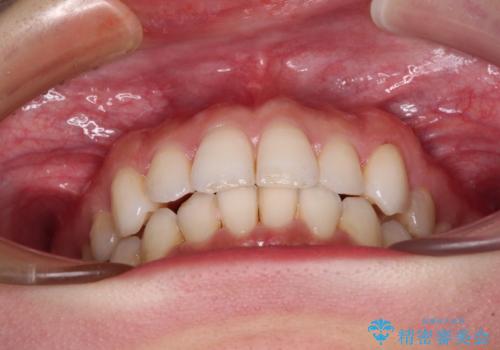

1日22時間の装着時間を守ってくださったので、比較的早く治療を終える予定でしたが、各国での入国制限が厳しくなり、帰国のタイミングに合わせてのんびりと治療を進めることとなってしまい、やや長期間の治療となりました。